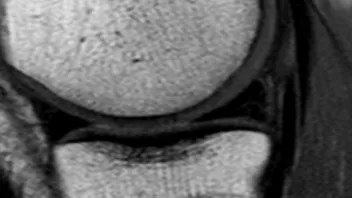

Ich lerne immer mehr Menschen mit kaputten Knorpeln kennen. Besonders vom Abbau betroffen sind die Knie und die Bandscheiben.